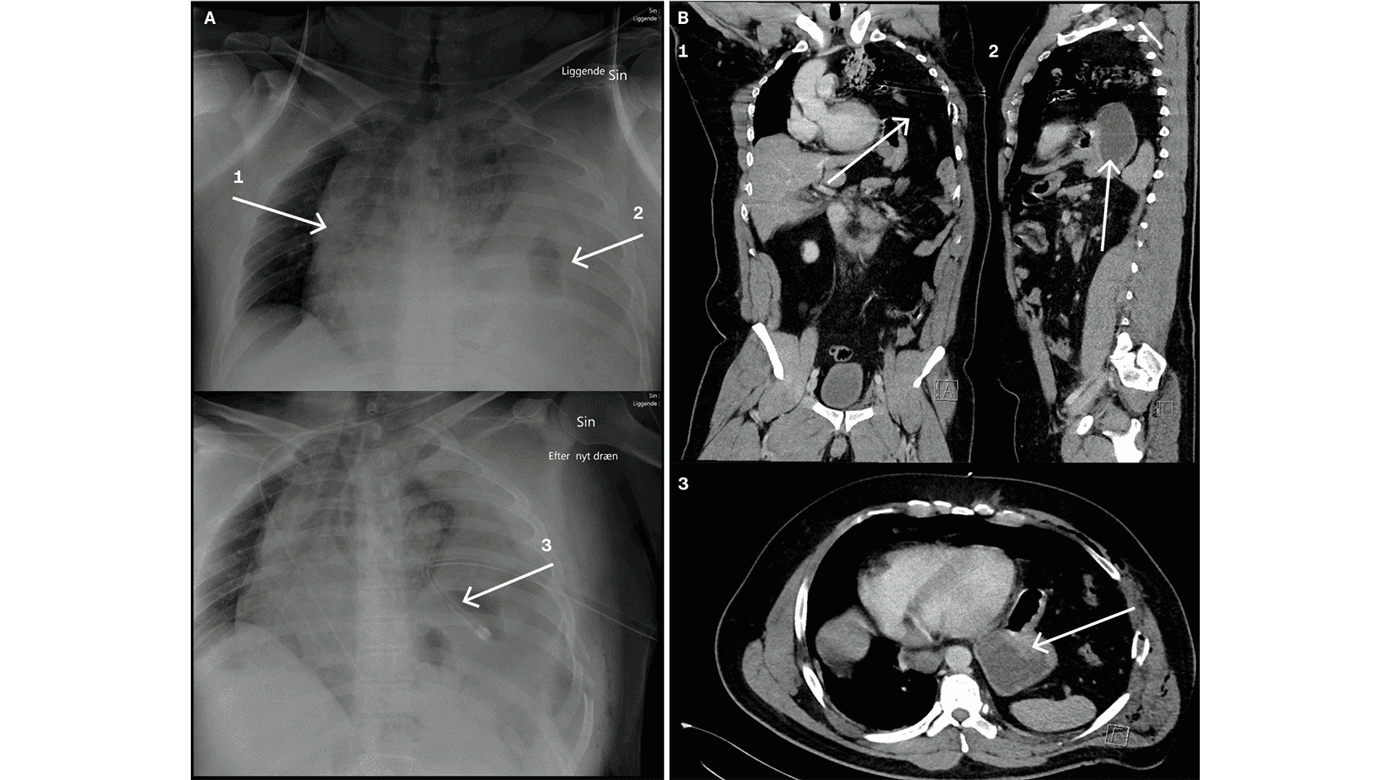

En 38-årig mand var involveret i en trafikulykke og havde bl.a. pådraget sig en venstresidig diafragmaruptur med herniering af colon, ventrikel og milt op i thoraxhulen. A viser traume-CT med hhv. 1) koronalt plan, 2) sagittalt plan og 3) aksialt plan af diafragmaruptur og herniering af abdominalorganer op i thorax. Pilene peger på intraabdominale organer i thoraxhulen på niveau med hjertet. Dette gav forskydning af mediastinum mod højre. Patienten udviklede en svær obstruktiv shocktilstand. Tilstanden lignede til forveksling traumatisk hjertetamponade eller en trykpneumothorax grundet den mekaniske kompression af de intratorakale organer [1, 2]. Der blev taget røntgenbilleder, anlagt et pleuradræn uden effekt, og patienten blev overflyttet til traumecenteret. Der blev foretaget en akut laparotomi med hurtig reponering af de intraabdominale organer. Herefter forsvandt den obstruktive shocktilstand. Diafragmarupturen blev sutureret med nonresorberbar sutur, og det postoperative forløb var ukompliceret. Røntgenbillederne i B viser 1) mediastinal overskydning med trachea devierende mod højre, 2) luftholdigt intraabdominalt organ og 3) intraperitonealt anlagt pleuradræn. Normalvis forventes luftfyldt lungehule på den afficerede side ved pneumothorax, hvilket står i kontrast til B.